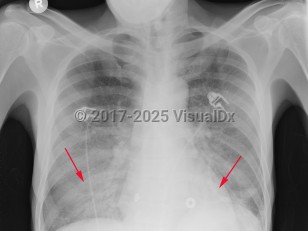

Imaging Studies image of Pneumocystis jirovecii pneumonia - imageId=2956223. Click to open in gallery.  caption: 'Frontal chest x-ray with diffuse, bilateral ground glass opacities with progression to air space consolidation, worse in the lower lobes.'

Frontal chest x-ray with diffuse, bilateral ground glass opacities with progression to air space consolidation, worse in the lower lobes.